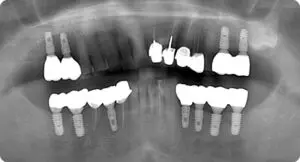

主治醫師:鄧本暉 醫師 病患自述上下後側都缺了很多

主治醫師:蔡忠澍 醫師 病人上下全口缺牙,導致病人

主治醫師:蔡忠澍 醫師患者因上顎全口缺牙、下顎部分